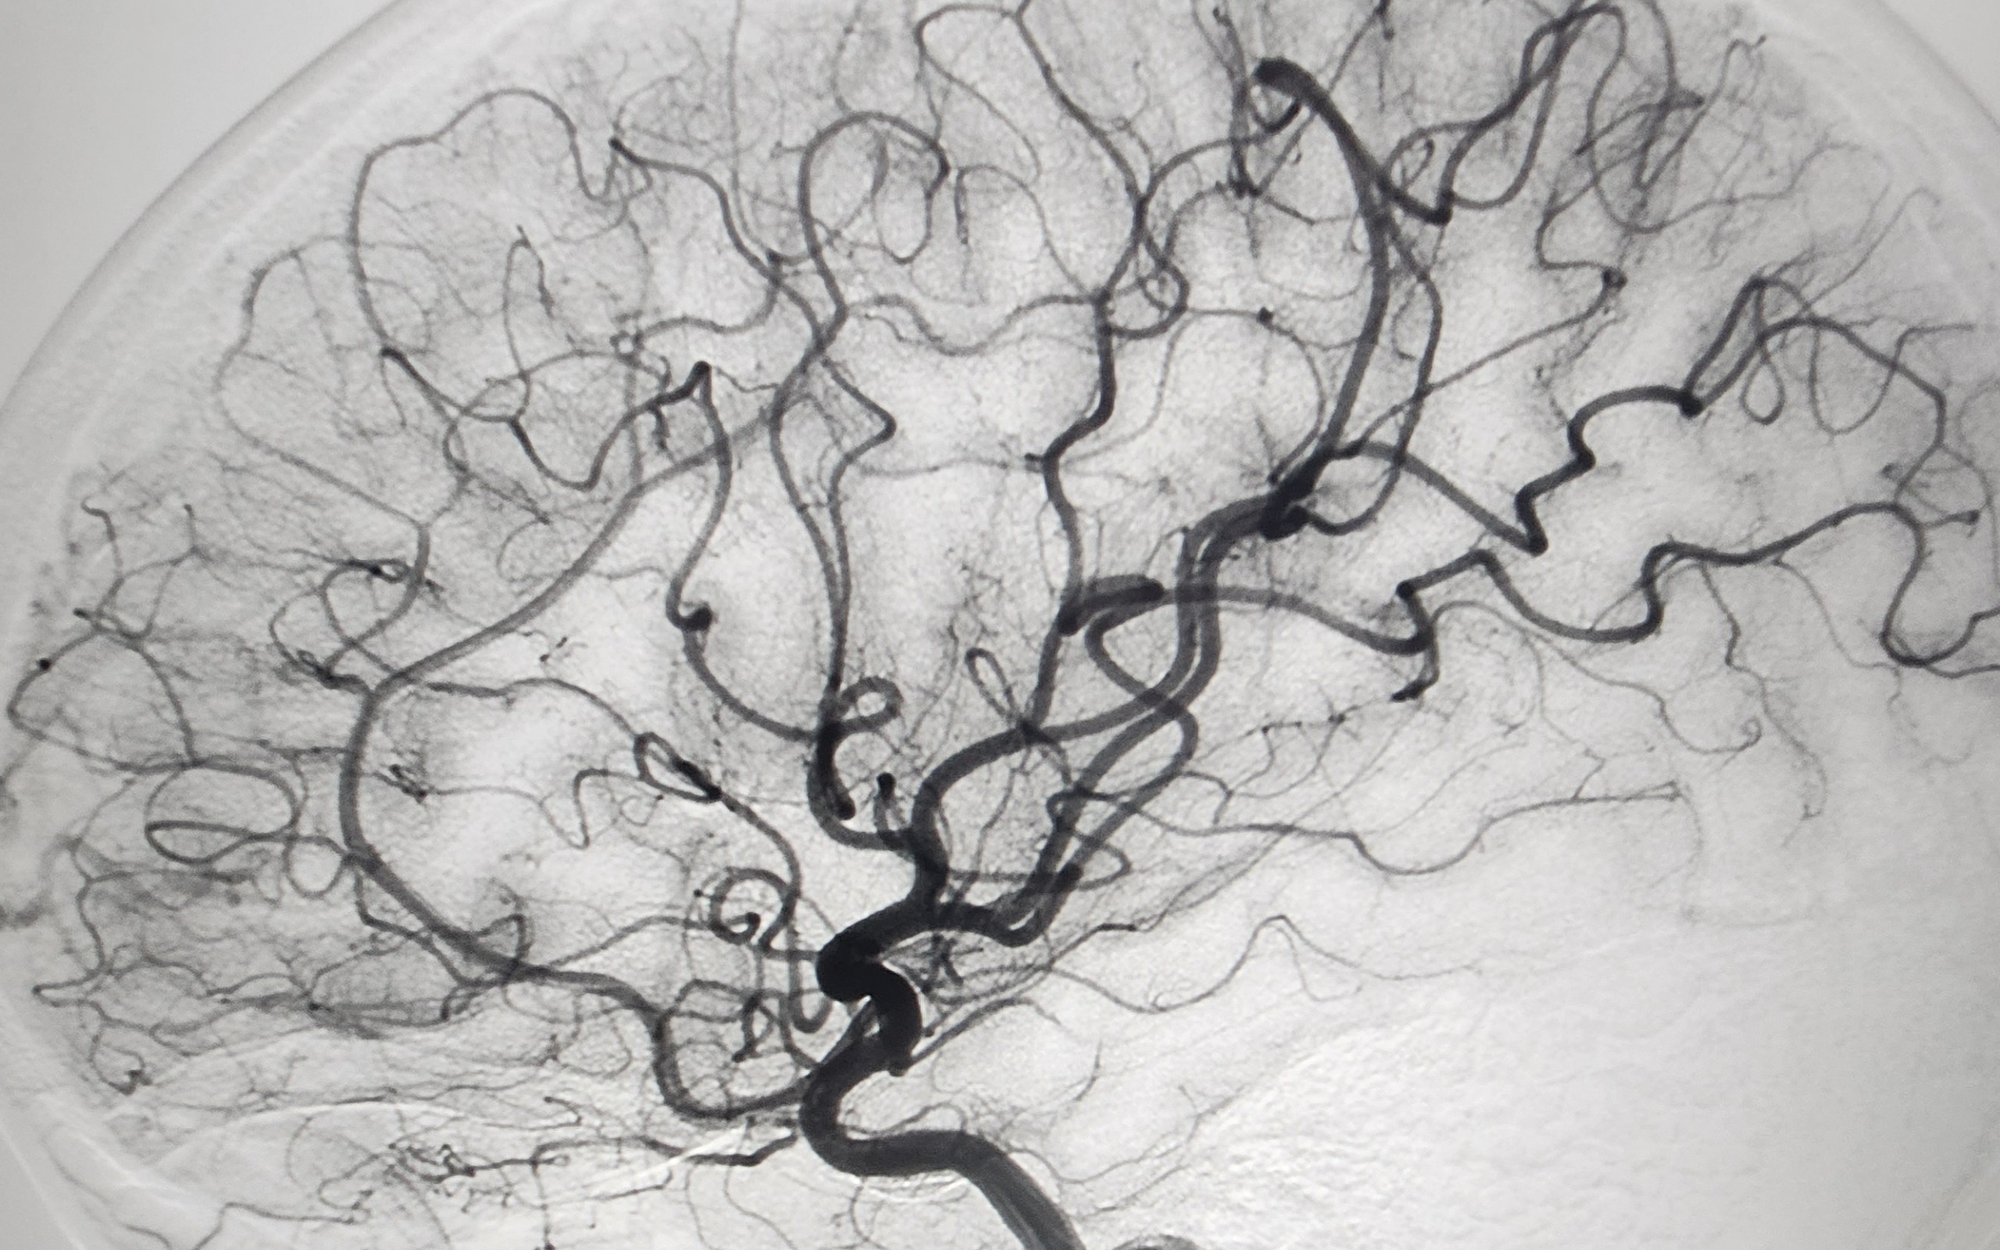

Tại Bệnh viện Chợ Rẫy, hầu hết các kỹ thuật can thiệp nội mạch chuyên sâu đã được triển khai, như: Can thiệp mạch não cho bệnh nhân đột quỵ, phình hay tắc mạch não; Can thiệp mạch tạng, tĩnh mạch cửa, tắc mạch trong ung thư gan; Nong, đặt stent mạch máu ngoại biên cho bệnh nhân tiểu đường, thiếu máu chi.

Can thiệp nội mạch đòi hỏi trang thiết bị hiện đại như hệ thống máy DSA và vật tư y tế chuyên dụng, nên hiện vẫn là kỹ thuật chuyên sâu, chỉ thực hiện được ở một số bệnh viện lớn. Tuy nhiên, ngành y tế đang hướng đến mở rộng mạng lưới triển khai về tuyến dưới, giúp người bệnh ở các địa phương được tiếp cận điều trị sớm, đặc biệt trong các ca cấp cứu như đột quỵ – khi "thời gian là vàng".